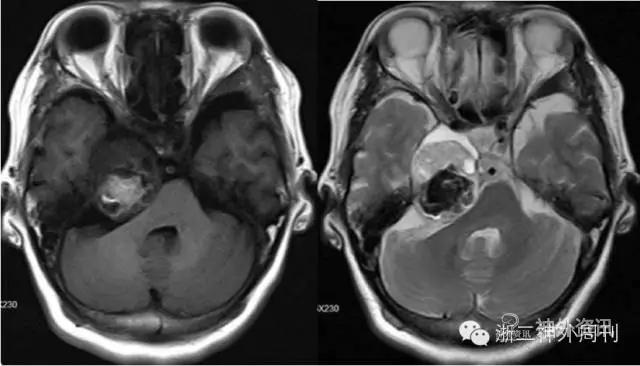

入院后进一步行头颅MRI增强检查,显示右侧鞍旁沿岩骨上方跨中后颅窝生长囊实性占位,大小约32mmx38mmx32mm,实性部分T1WI呈等低信号,T2WI呈高于脑实质信号,其内混杂团块状短T1短T2出血信号区,其前内侧见半环状类脑脊液液性信号,病灶占据右侧Meckel腔,边界清,后缘压迫脑桥及右侧小脑中脚。增强后实性部分中等强化,右侧卵圆孔增大。右侧三叉神经脑池段显示不清,右侧面听神经未见异常。

影像诊断:右侧Meckel腔及桥小脑角区占位,考虑三叉神经瘤伴出血可能大(图1)。

图1. MRI增强检查显示右侧颅中窝底及后颅窝骑跨型肿瘤。